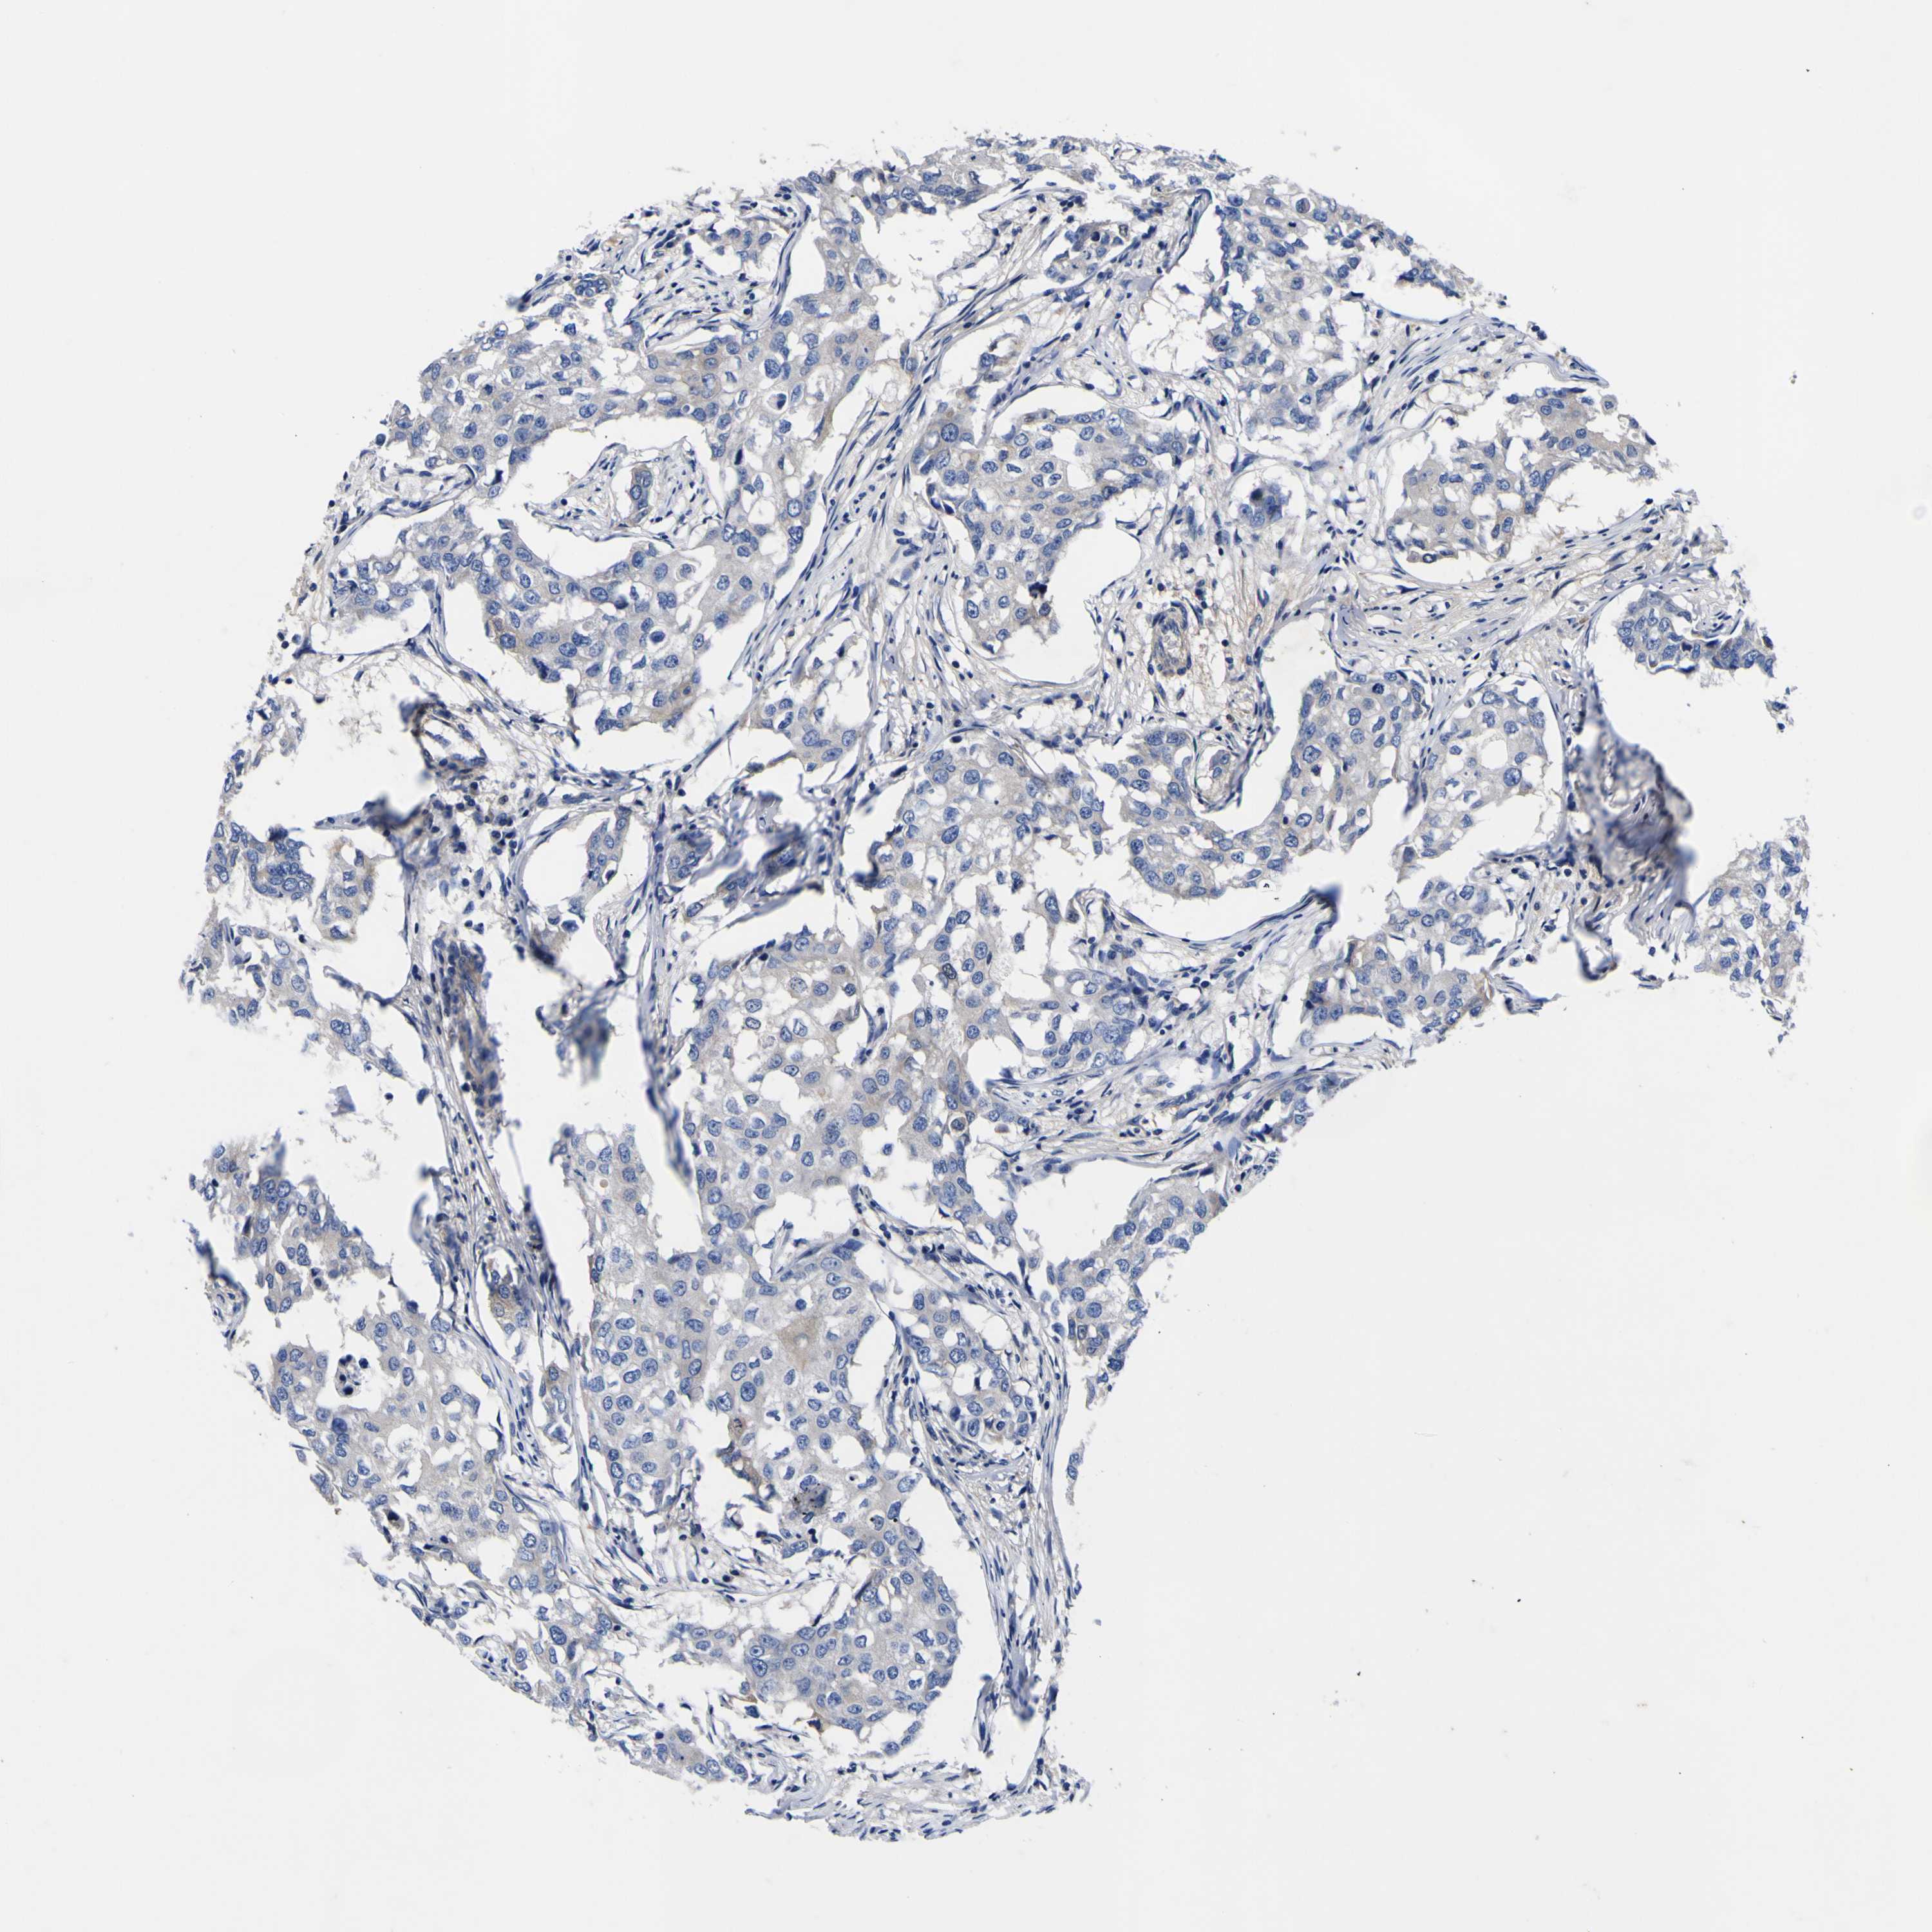

CANCER BREAST CANCER Show tissue menu

BRCA TCGA BRCA VALIDATION PROTEIN EXPRESSION